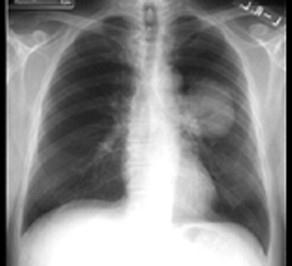

胸片如图所示,这种典型的X线征象以下列哪种疾病可能性最大 ( )A、肺部良性肿瘤B、支气管扩张C、中心型肺癌D、肺结核E、周围型肺癌

问题 胸片如图所示,这种典型的X线征象以下列哪种疾病可能性最大 ( )

选项 A、肺部良性肿瘤 B、支气管扩张 C、中心型肺癌 D、肺结核 E、周围型肺癌

答案 C